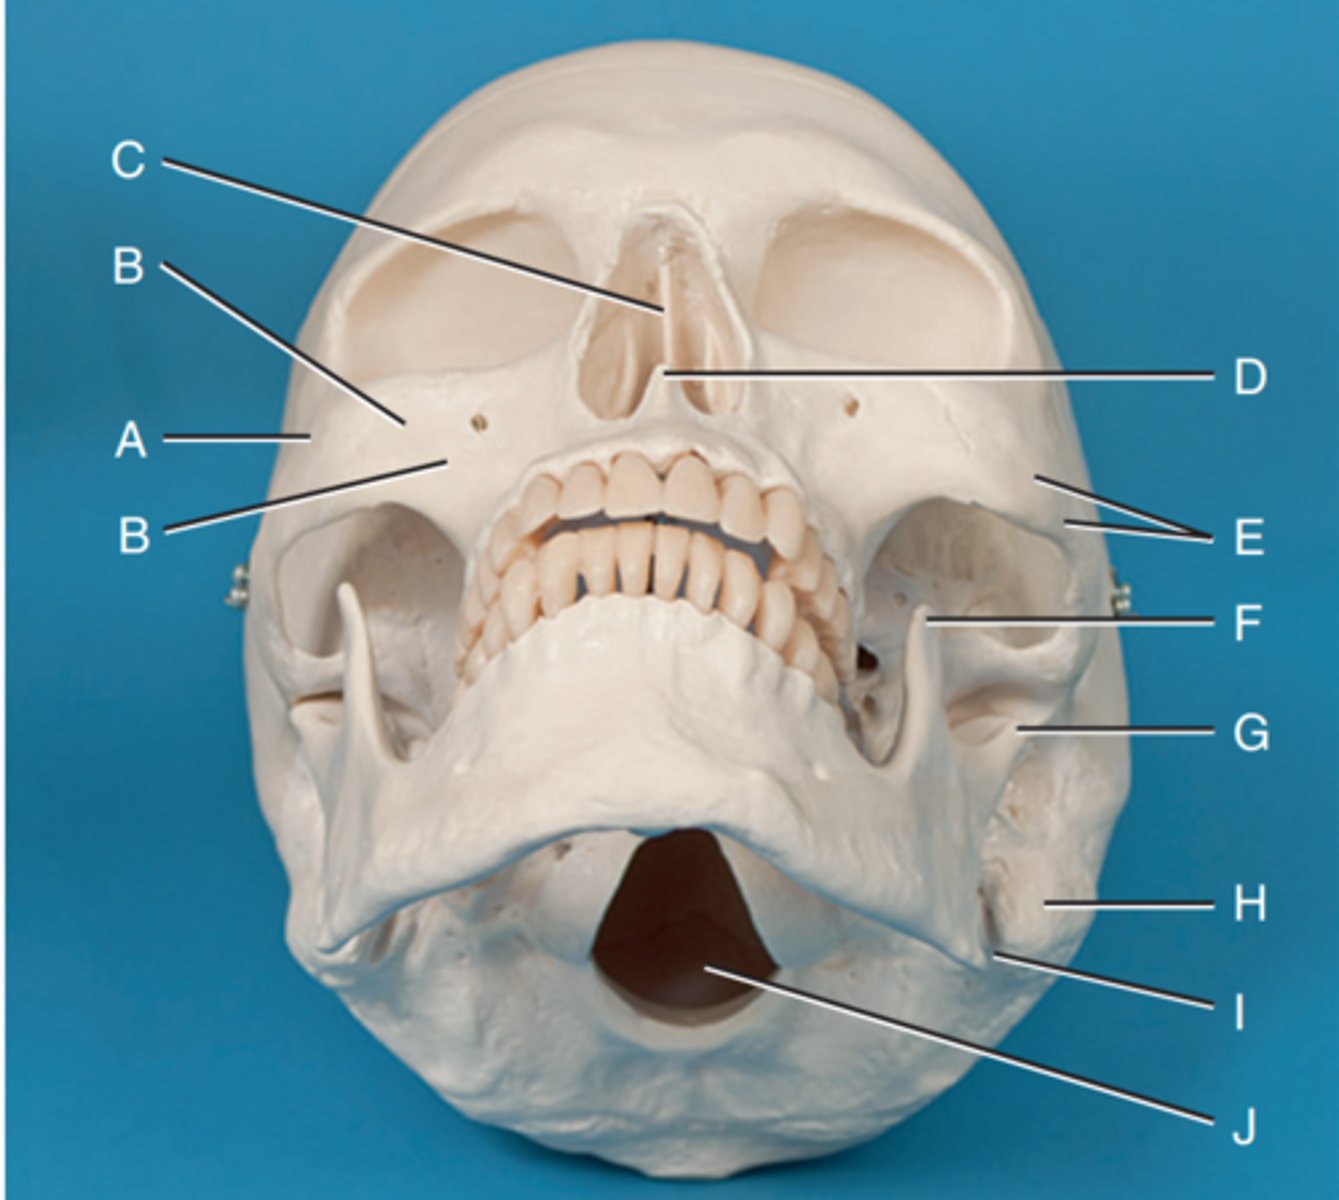

Zygomatic prominence

Label A

Body of maxilla

Label B

Bony nasal septum

Label C

Anterior nasal spine

Label D

Zygomatic arch

Label E

Coronoid process

Label F

Condyle

Label G

Mastoid process of temporal bone

Label H

Angle of mandible

Label I

Foramen magnum

Label J